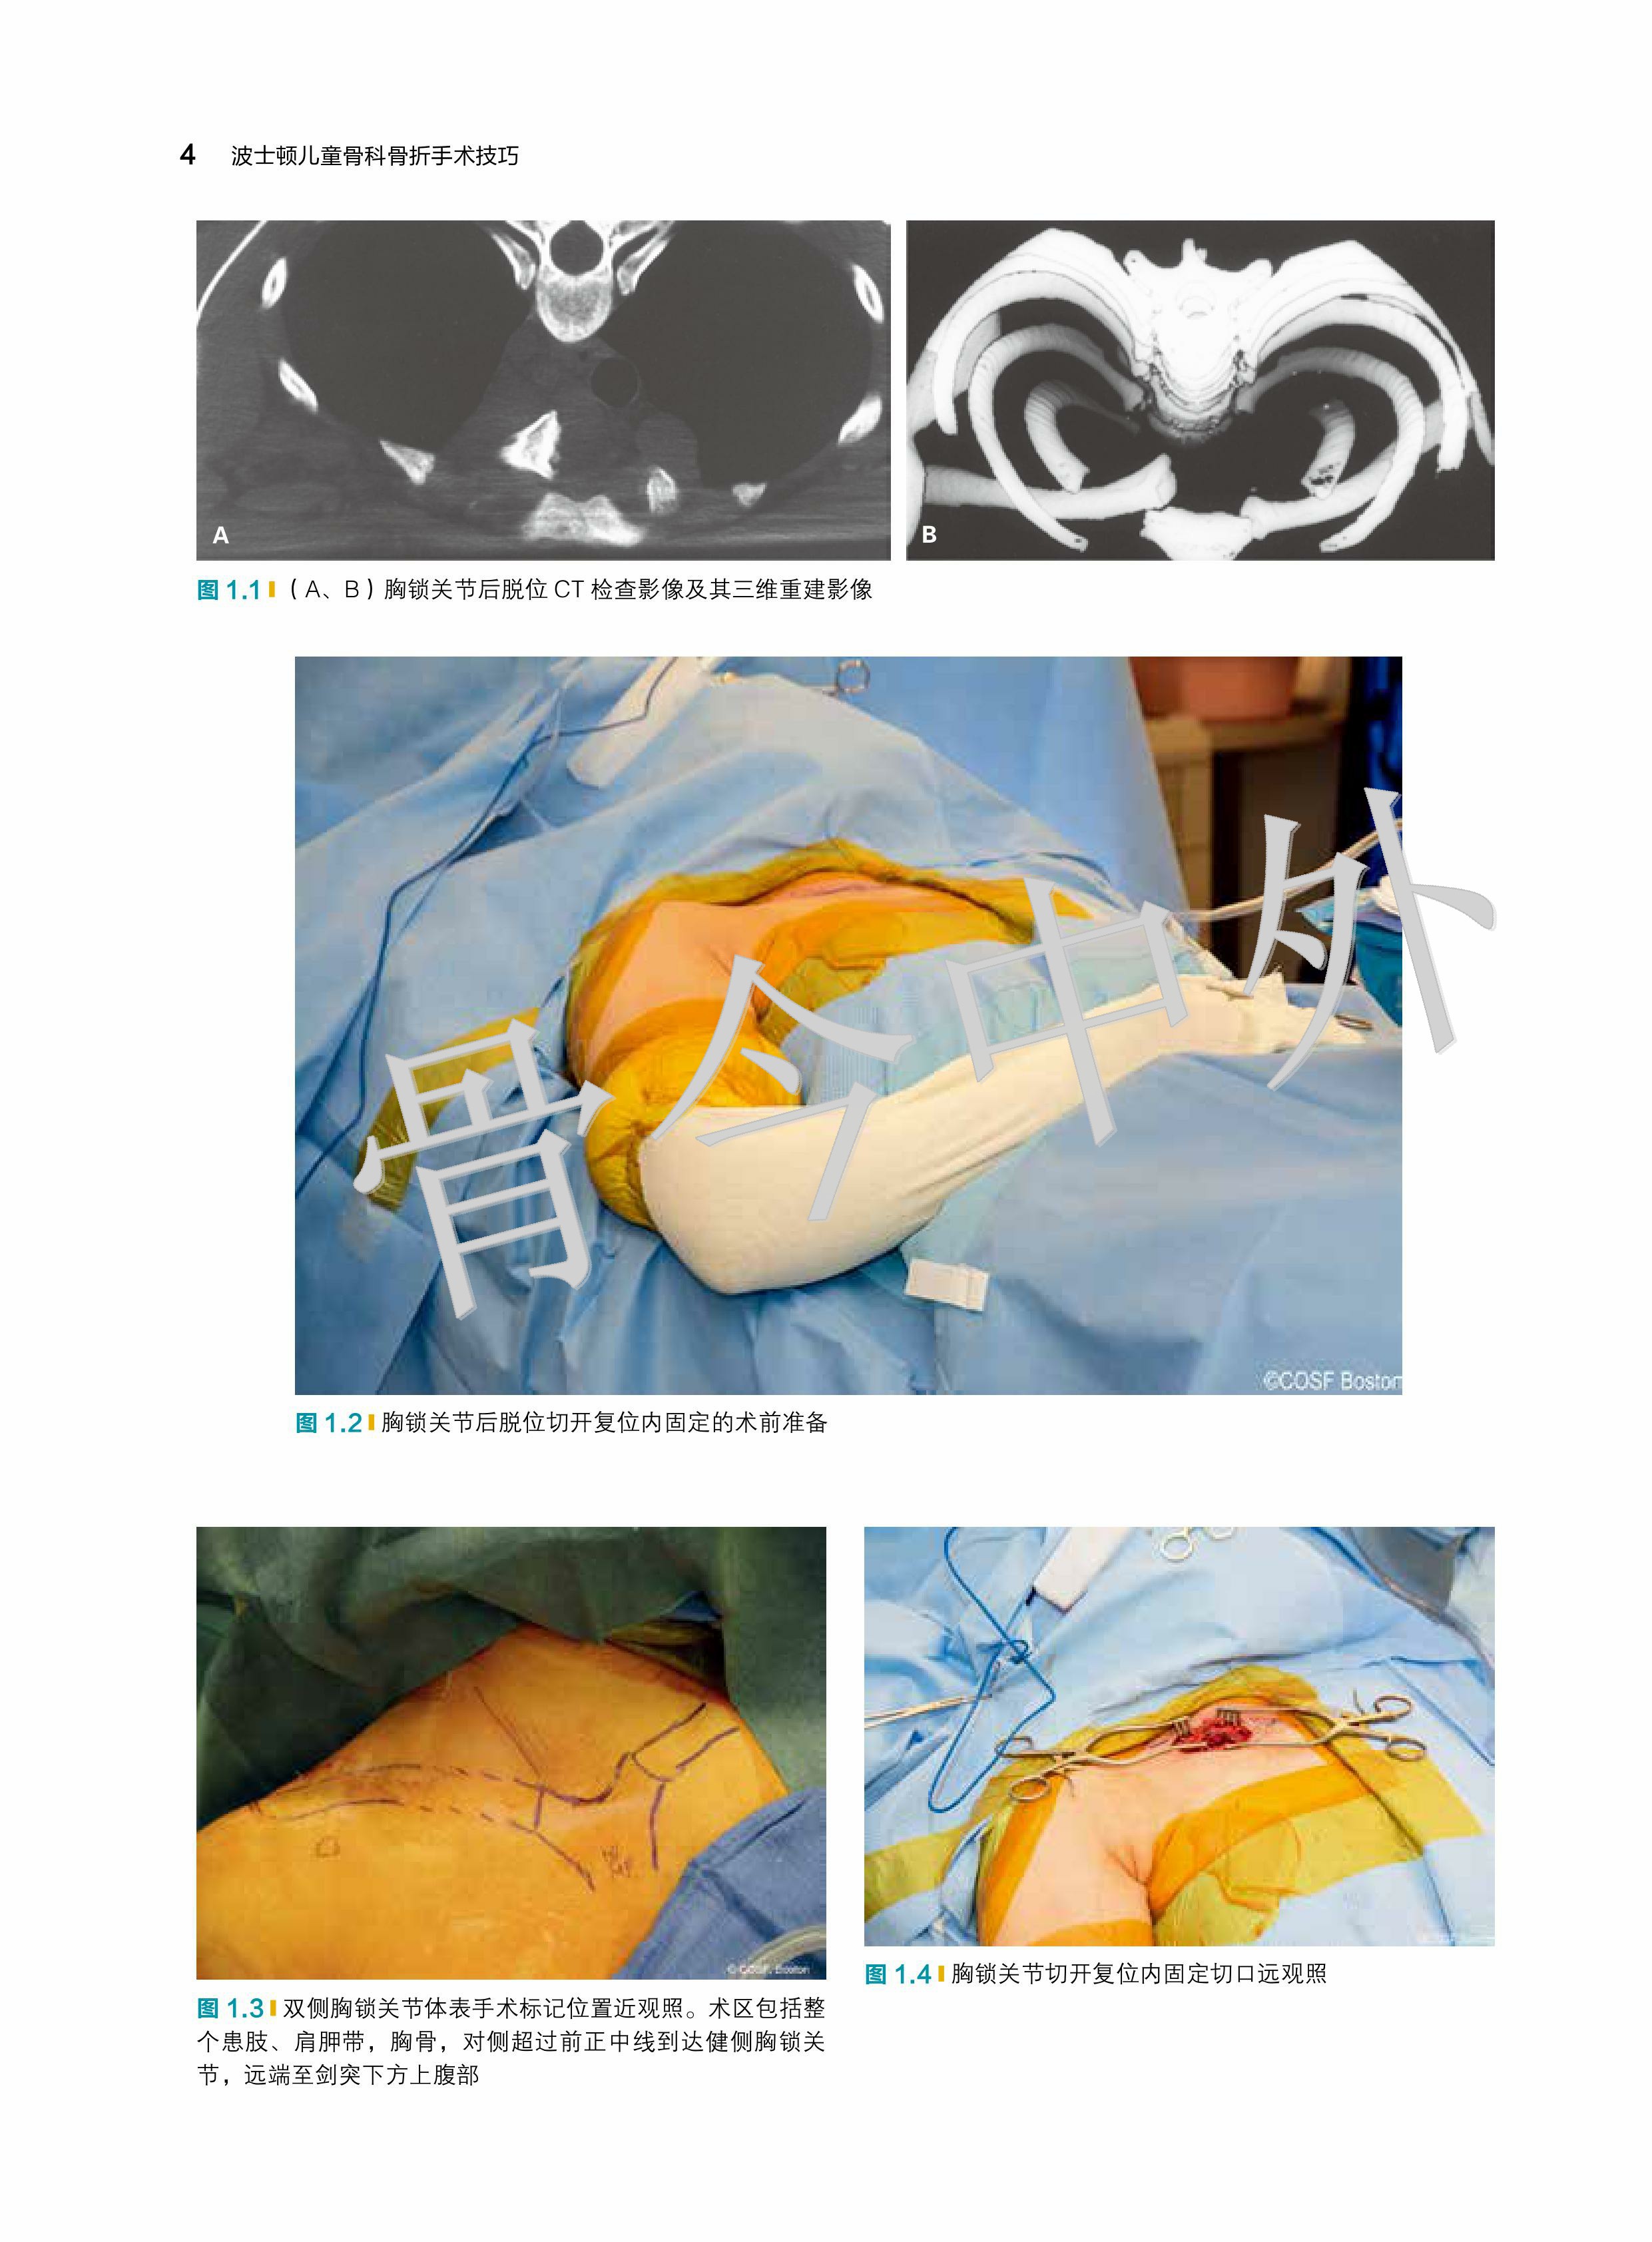

★ 内页插图 ★